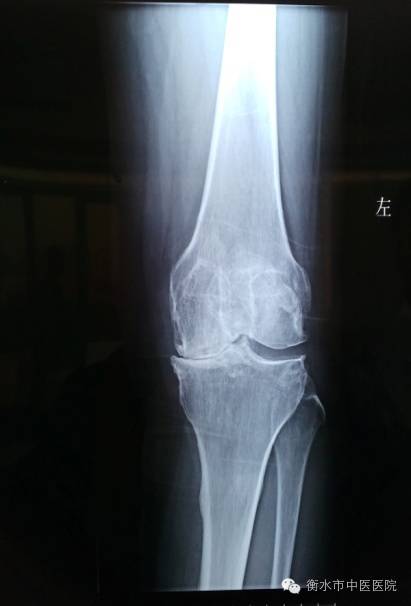

膝关节骨性关节炎是指由于膝关节软骨变性、骨质增生而引起的一种慢性骨关节疾患,主要表现为膝关节疼痛和活动受限,严重者可出现膝内翻畸形,X线表现为关节间隙变窄,甚至消失,软骨下骨质致密,骨小梁断裂,有硬化和囊性变。膝关节骨性关节炎如果发展到膝内翻畸形,将严重影响患者的生活质量,给患者带来很大的痛苦。这一阶段的治疗一般采用保守治疗,如理疗、药物、注射疗法和中医中药治疗等,这些疗法只能帮助患者缓解一时的痛苦,而且效果往往不能令患者满意。近年来,随着科技的进步,人工膝关节置换术成为治疗此类疾病的主要选择,但此种治疗方式同样存在手术费用高、置换关节有使用年限限制、患者需忍受巨大痛苦等弊端。孟氏固定架外固定术+胫骨上段高位截骨恰好解决了这一难题,骨伤科在独家引进此项技术后,采用中西医结合对患者进行治疗,经过多年临床应用和实践,普遍反映痛苦小、手术费用低、术后恢复快,深受患者的信赖。

【病例】骨伤科在与北京望京医院骨伤科成为协作科室后,积极吸取先进经验和技术,与2016年1月27日邀请望京医院骨伤科金阳主任医师亲自为在我院治疗的一名经受膝关节内翻畸形多年病痛折磨的45岁女性住院患者进行了胫骨上段高位截骨+孟氏固定架外固定术,不仅为患者矫正了膝内翻,解除了病痛,而且大大降低了治疗费用,现患者已可以正常下床活动。

(术前)